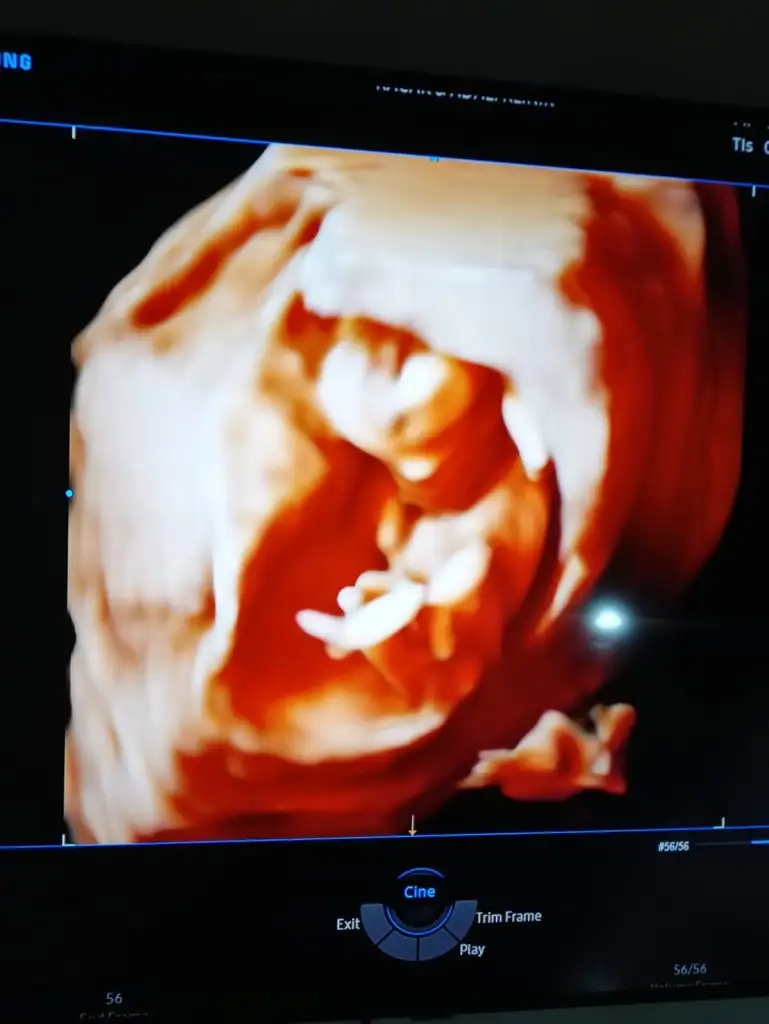

Merhaba detaylıda kız dedi doktor, anketi doğru tahmin olarak işaretledim. Teşekkürler😁

Saglıkla gelsin prenses 😊😊 ilk kız dedim teyit etmek için başka usg istemiştim. Teşekkurler dönüşler için 😊